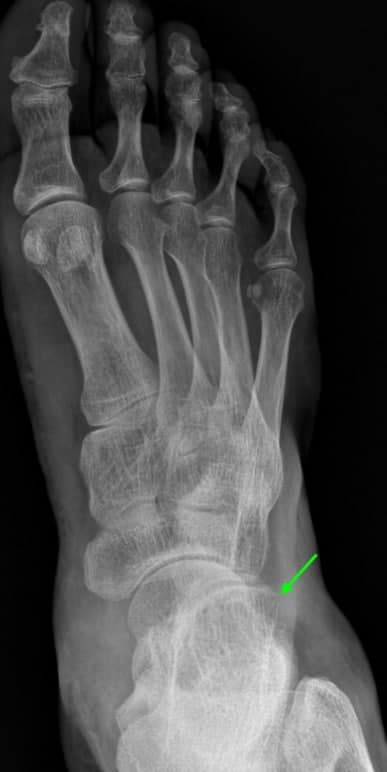

위 환자분은 오전 10시경 화곡역 계단에서 발목을 접질린 후 발등 통증으로 정형외과에서 X-ray 검사를 받으셨습니다. 담당 전문의 선생님께서 X선 판독을 보시고는 뼈는 괜찮고 인대가 늘어났다고 진통소염제를 처방해주셨습니다. 원래 다른 부위를 치료받던 환자분이라 영상CD를 복사하여 11시쯤 바로 한의원으로 걸어서 내원하셨습니다.

## 엑스레이를 꼼꼼하게 살펴보니 골절선이 명확하게 보이지 않았습니다.환자분의 발목에서 부어있는 곳을 2mm단위로 바둑판처럼 촘촘하게 하나 하나 눌러서 아픈 부위를 찾아봤습니다. 환자분께서 통증을 호소하는 곳은 종골이라는 뼈의 앞쪽 돌기였습니다. 발목을 접질렀을때 인대가 늘어나면서 파열도 잘 생기는 곳이고, 뼈를 잡아당기면서 골절도 자주 생기는 부위입니다. ## 무엇보다 제일 큰 문제는 종골 전방돌기가 엑스레이상 뼈가 겹쳐보여서 실금(미세골절), 견열골절이 잘 보이지 않는다는 것입니다. 걷는데 큰 지장이 없고, 인대를 늘려봤을 때 많이 아프지 않다고 하셔서 미세골절 가능성을 충분히 설명해드리고 MRI보다 CT 검사를 권고 드렸습니다. ## 작은 뼈 조각은 MRI에서 보이지 않기 때문에 뼈를 위주로 관찰하는 CT 검사가 골절 진단에 더 적합합니다. 만약 걷기가 어렵고 스트레스 검사상 통증이 심하다면 주변 인대, 근육, 연골 손상이나 뼈에 멍이 드는 골수 부종도 있을 수 있어 MRI 검사를 같이 실시해야 합니다. 어떤 검사를 하면 좋을지는 의학적 전문지식이 필요한 영역으로 진료의가 결정해드립니다..그러니까 크게 고민하지 않으셔도 괜찮습니다.

골절의 가능성이 있으므로 비탄력 테이핑으로 발목을 단단하게 고정하고 협력병원으로 즉시 CT검사를 의뢰하였습니다. ## X-ray를 찍은지 2시간 뒤인 12시반쯤 시행한 CT검사에서 종골 전방돌기의 골절로 진단되었습니다.

위 사진처럼 발등 골절이 좌측 X-ray에서 보이지 않았지만, 우측 CT에서는 보입니다.초기 미세골절, 견열골절, 실금은 단순 방사선 검사인 엑스레이에서 잘 보이지 않습니다.그렇다고 CT가 완전한 골절 진단법일까요?아닙니다. 연식이 오래된 예전 CT 검사에서는 2mm 이하의 작은 뼈 조각은 안 보일 때도 있습니다. 그래서 가급적 최신 640 CT나 초음파검사로 골절 의심부위를 촘촘하게 단면을 확인해보는 것이 좋습니다.**